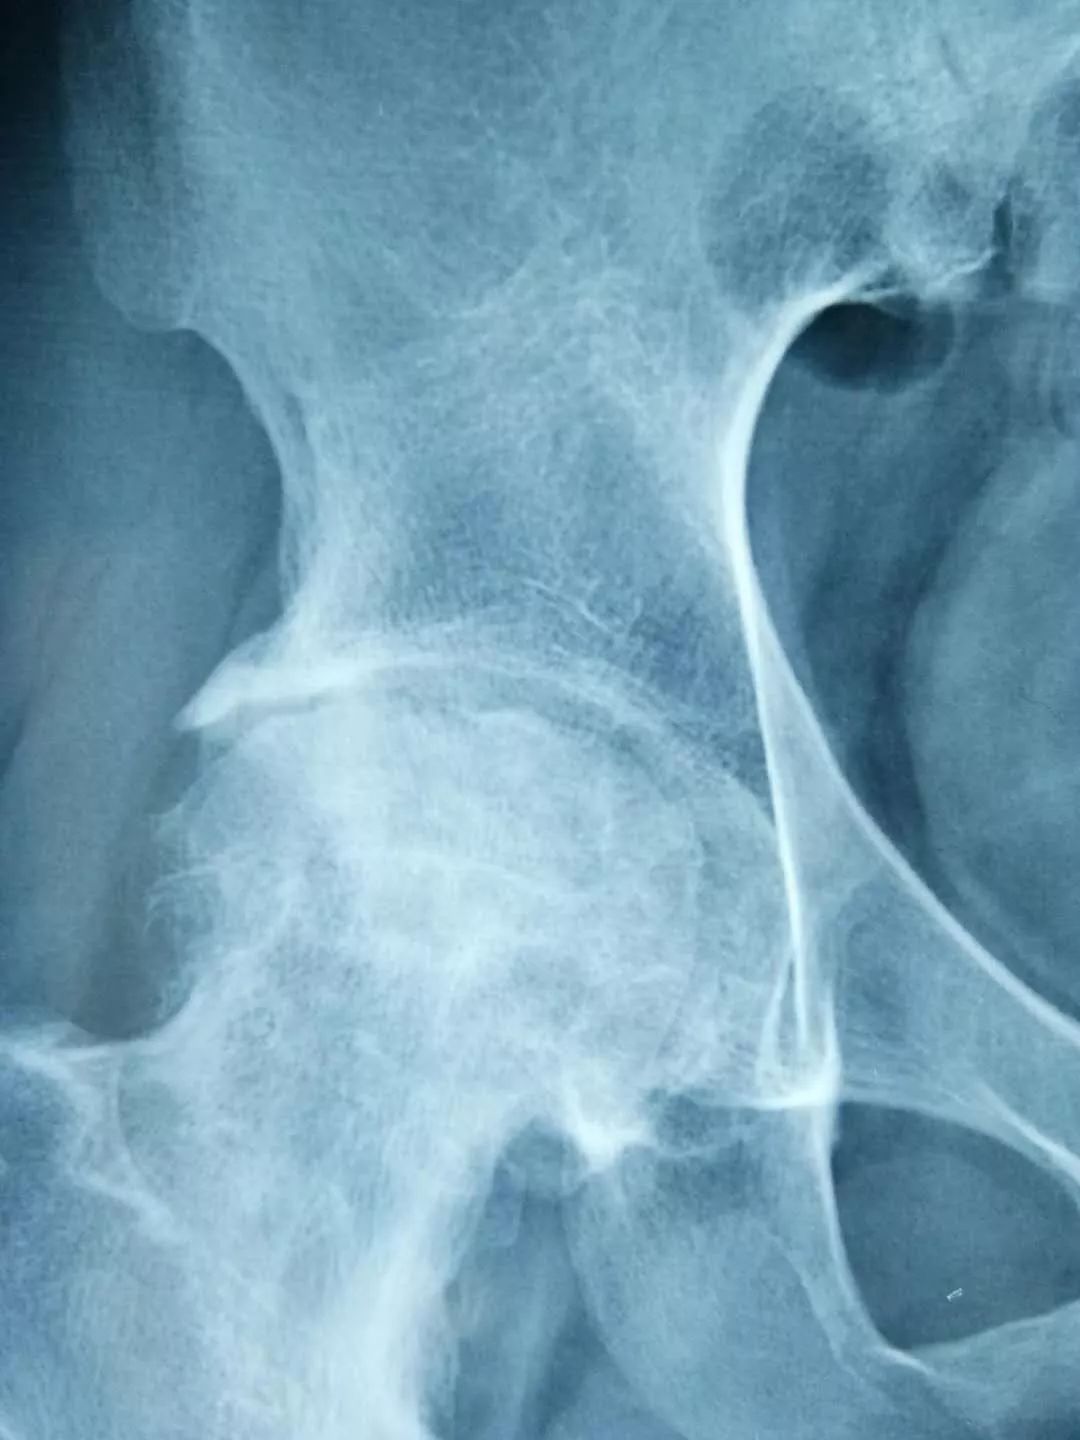

青岛患者张先生50岁出头就患上了双侧股骨头坏死,病程3期,多个医院给出的治疗方案均是置换人工关节,张先生不能接受,经人介绍找到廉从希。廉从希以红花、人参、鹿茸、阿胶、当归等生血散寒、除湿祛瘀的中药配伍令其内服,以马钱子、川乌、秦艽、元胡、透骨草、土元等20余味道地药材炼制成膏药令其外敷,并结合切肤骨蒸方法令疗效最大吸收。一个疗程后患者症状便明显好转,坚持治疗3个月后去医院检查,股骨头坏死症状完全康复。

一名*安泰**的女性股骨头坏死患者,在儿女强力怂恿下来淄博找廉从希求医,一开始对“廉氏三联疗法”并不抱太大信心,但一个疗程结束后,患者便惊喜地发来医院检查的骨片,股骨头坏死部位纹理已明显开始致密均匀,病情有了很大好转。患者自此坚定了治疗信心,持续治疗3个月后痊愈。

经对118名患者跟踪调查,“廉氏三联疗法”对股骨头坏死的总有效率在92%以上;显效率(症状明显好转,功能障碍恢复)87%以上;病理改善率(影像显示骨密度增强)83%以上;临床治愈率(视察一年以上,症状消失,功能障碍恢复,可做日常家务及轻体力劳动)75%。

左图为治疗前,右图为治疗后。